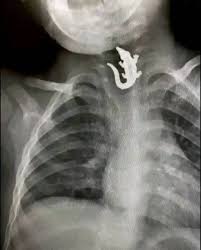

Image Description (Peptic Stricture): A barium swallow showing a smooth, tapered, focal area of narrowing in the distal esophagus, commonly caused by chronic acid reflux.